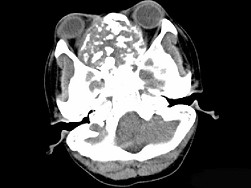

男性,28岁,因鼻塞、头痛1年余,鼻窦CT扫描如图所示,请选择正确的描述与结论 ( ) EBH-00091.jpg EBH-00092.jpg EBH-00093.jpg EBH-00094.jpg

• A.肿块内密度不均,有较多致密钙化影

• B.窦壁及颅底骨质破坏

• C.双侧上颌窦、筛窦、鼻腔及蝶窦内见软组织肿块影

• D.考虑为鼻窦软骨瘤

• E.考虑鼻窦骨瘤